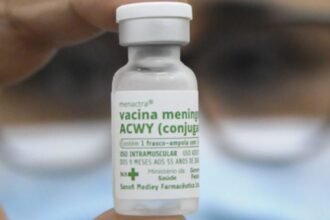

Meningite: entenda como fica vacinação com ACWY após mudança nas doses

Desde o início da semana, crianças com 12 meses de vida já…

Mudança na vacinação contra a meningite ACWY passa a valer hoje

A partir desta terça-feira (1º), a vacina meningocócica ACWY passa a ser…